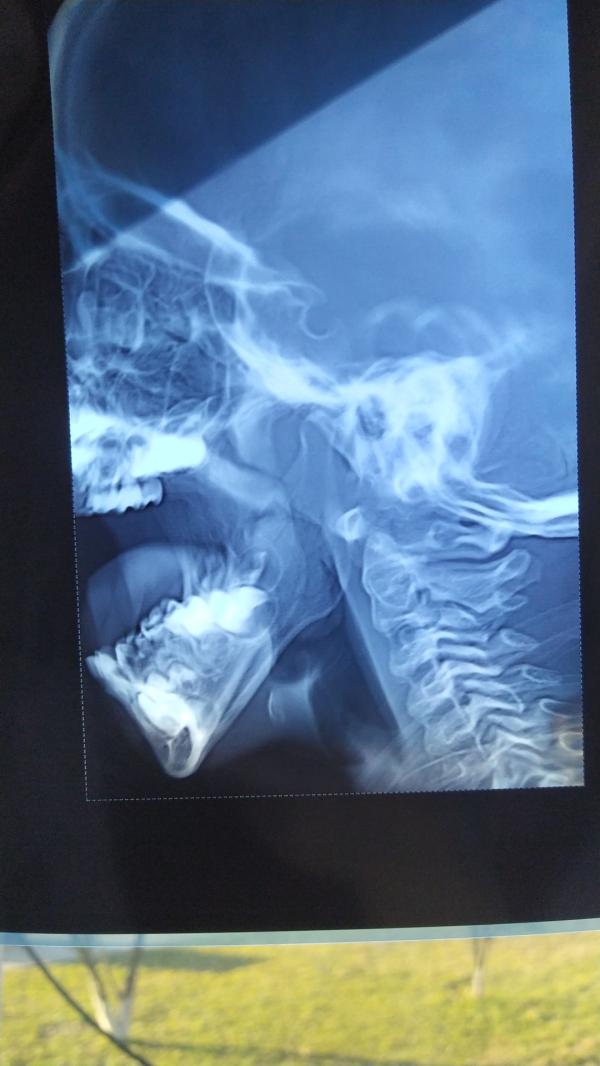

Ассаламу алейкум.Девочки , срочно нужен совет,нам сказали нужно делать операцию по удалению аденоидов, полностью перекрыта носоглотка.В какую больницу мне лучше обратиться.Сыну 4,5 года.Кто сталкивался с этим поделитесь.

Другим тоже показала, срочно оперировать сказали